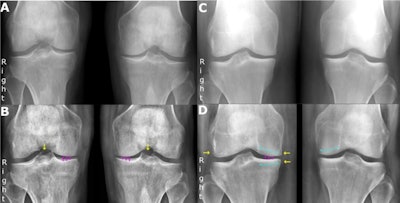

The researchers retrospectively enrolled 50 consecutive patients with weight-bearing, nonfixed-flexion posteroanterior radiographs of both knees (100 knees) acquired at their hospital between September 2019 and October 2019. A research radiographer reviewed all images to ensure a full range of osteoarthritis severity was covered under the Kellgren and Lawrence system, which offers five grades, from normal to severe.

Six radiology professionals were included as readers: two musculoskeletal specialists with more than 10 years of clinical experience each, two reporting technologists with more than 10 years of musculoskeletal reporting experience but no prior experience with the Kellgren and Lawrence system, and two resident radiologists. The AI tool acted as the seventh reader.

Analysis revealed agreements between the AI tool and the consensus between the two musculoskeletal specialists was 0.88, while agreement between the specialists themselves was 0.89, according to the findings.